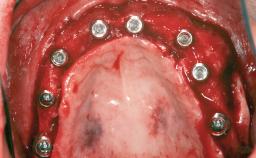

# of Implants 8

Type of Implants Reduced-Diameter|Two-Piece

Bone Augmentation Horizontal|Sinus Floor Elevation|Staged|Vertical

Augmentation Materials Autogenous chips|Autogenous block(s)